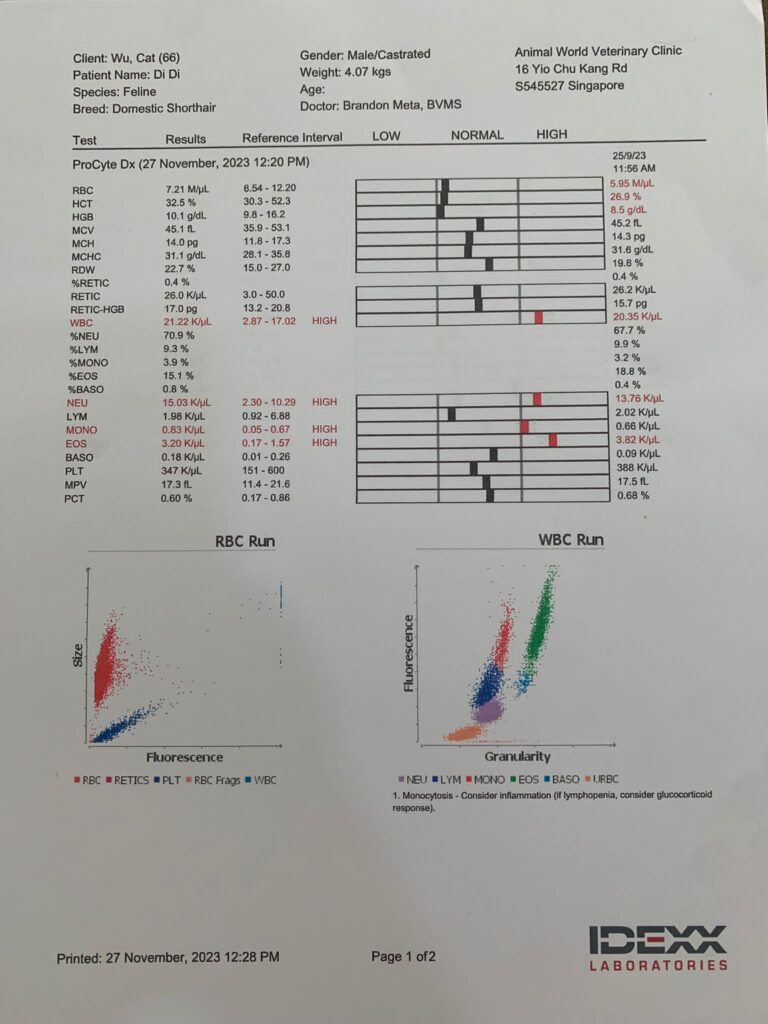

27 Nov 2023

1150am: see dr Brandon

4.07kg – lose 280g in 50 Days

Hct kidneys liver lytes all ok. Only glob and glu higher most prob due to stress/ mouth. Nothing else I can do. Exactly why I know didi is under the category of no need to see vet cos nothing significant can be found n done. Have to whack more money on bupre. dr told me to try im for better absorption. He tried open his mouth – fail badly. Too pain.

I think I need to recheck his glucose. But for now his lytes ok I’ll continue Subcut.

Cbc out: Eos high again – dr wants him to be dewormed. Hct 26.9%, going up, wbc 20.35 going down doxy to continue for total 21 days.